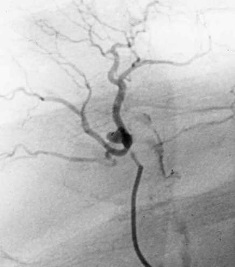

栓塞导管的选择 在诊断性血管造影后,血管造影导管可以直接前进到靶血管位置进行栓塞。亲水导管和导丝可以使导管头前进的末梢的血管。使用标准的血管造影导管进行栓塞常见于肾动脉,肝动脉,脾动脉和髂内动脉的栓塞。使用的栓子包括明胶海绵块,明胶海绵颗粒,明胶海绵粉,弹簧栓,酒精等。一般常见的微导管有4种,Tracker-18, Tracker-325, MicroFerret-18,SP导管。它们一般可以通过5F导管与之形成共轴导管系统。同时本身也能接受0.018英寸的导丝,以利于微导管的推送力和旋转的控制力。这些导管各有特点。可以允许直径300-800微米的颗粒通过。由于较细可以前进到更为末梢的血管,使栓塞更为有效和安全。 特殊导管包括球囊阻塞导管,可以在注射栓塞剂时防止栓子逆流和控制血流速度以利于动静脉畸形的栓塞。可脱球囊导管,可以进行海绵窦瘘的栓塞。